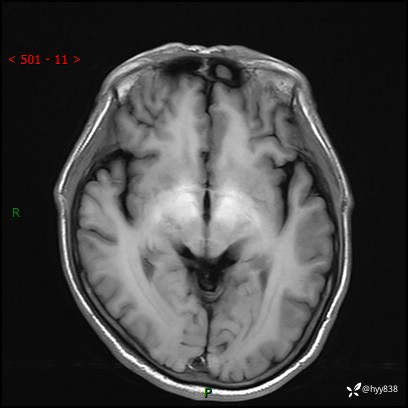

颅脑MRI平扫